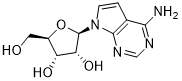

馬鞍山致研生物醫(yī)藥科技有限公司成立于馬鞍山市鄭浦港新區(qū)現(xiàn)代產(chǎn)業(yè)園。公司專(zhuān)注于生物小分子、醫(yī)藥中間體相關(guān)產(chǎn)品的研發(fā)和生產(chǎn),產(chǎn)品主要包括DNA亞磷酰胺單體、RNA亞磷酰胺單體、特殊單體以及按照客戶(hù)要求定制的RNA和DNA,并且公司提供定制合成等方面的研究服...

馬鞍山致研生物醫(yī)藥科技有限公司成立于馬鞍山市鄭浦港新區(qū)現(xiàn)代產(chǎn)業(yè)園。公司專(zhuān)注于生物小分子、醫(yī)藥中間體相關(guān)產(chǎn)品的研發(fā)和生產(chǎn),產(chǎn)品主要包括DNA亞磷酰胺單體、RNA亞磷酰胺單體、特殊單體以及按照客戶(hù)要求定制的RNA和DNA,并且公司提供定制合成等方面的研究服...